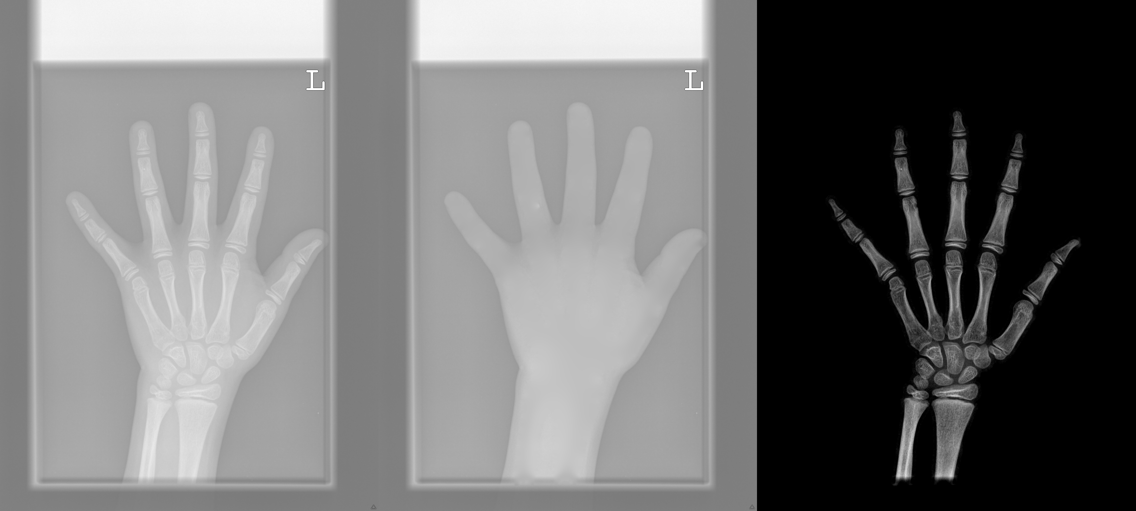

We performed three experiments for our method. First, we perform our method on several X-ray images, showing our method is not restricted by specific imaging objects. Second, we compared our method with image enhancement method and dehazing method, showing that our modification of the original dehazing indeed helps in this task. Third, we perform our method on a hand X-ray image dataset, showing its effectiveness and efficiency.

Several results from our method are shown in Fig. 7. The left column is the original input image. The right two columns are the soft tissue and bone image, respectively. It can be told that the soft tissue image is smooth as we assumed. Meanwhile, the bone image has better image contrast as desired. Moreover, our method can reach real-time performance on these X-ray images. The running time of our method on these images is reported in Table I.

In the third experiment, we applied our method on a hand X-ray image data set (RSNA), which contains more than 10,000 hand X-ray images. And the image has high resolution (usually larger than ). These images are collected from clinical applications. Therefore, we can apply our method on these practical images, showing the efficiency and effectiveness of our method on real high resolution images.

In each panel of Fig. 10, the input image (left) is decomposed into soft tissue (middle) and bone image (right) by our method. Although we only show the first ten images from the data set, the results for the rest images are similar.

The bone images have better image contrast since the parameter is theoretically guaranteed. Such enhancement can also be directly told by radiologists. Such enhancement is good for bone diagnosis in practical applications.